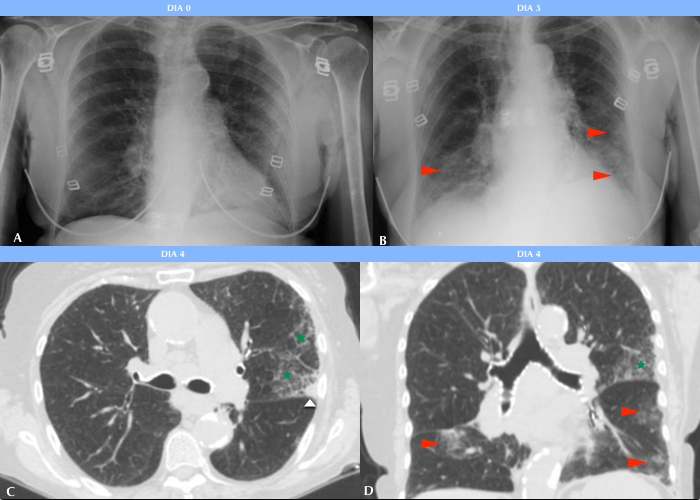

Se pudo estudiar la evolución radiológica de esta enfermedad en uno de los pacientes cuya evolución clínica fue tórpida, observándose en una radiografía inicial sutiles áreas parcheadas en vidrio esmerilado en campos pulmonares inferiores, las cuales fueron progresando hasta volverse coalescentes, difusas y consolidativas, llegando a afectar la mayor parte del parénquima pulmonar, asociándose además a derrame pleural. El paciente requirió intubación orotraqueal al décimo día de internación, sin lograr mejorar su cuadro clínico, y se constató su deceso 10 días más tarde (Fig. 2).

Jacobi et al. (13) estudiaron las manifestaciones radiológicas de la COVID-19 observadas con Rx portátil y describieron que en el momento en que los infiltrados involucran la mayor parte del parénquima pulmonar en forma difusa es cuando el paciente comienza con falla respiratoria y requiere intubación mecánica, lo que pudimos comprobar en nuestro trabajo.